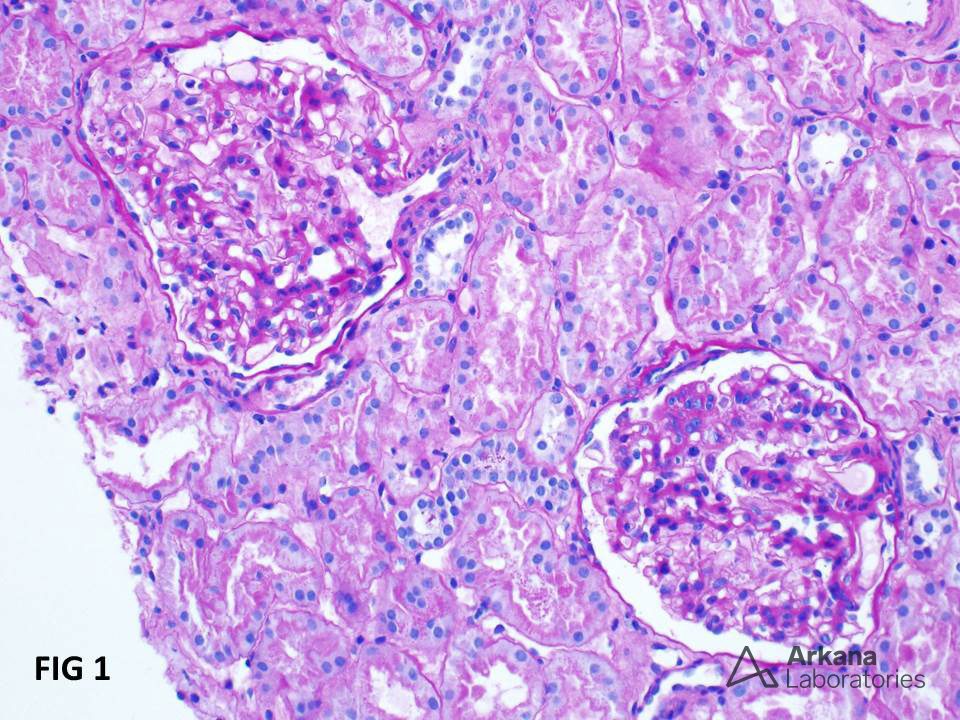

A alta da IRA realmente significa recuperação… ou apenas o começo da DRC futura? Albuminúria, reintrodução de IECA/BRA, iSGLT2 e seguimento precoce podem mudar completamente o prognóstico pós-IRA — e muita gente ainda foca só na creatinina da alta. Esse artigo do Clinical Kidney Journal traz 10 pontos práticos que todo nefrologista deveria revisar no seguimento pós-IRA.